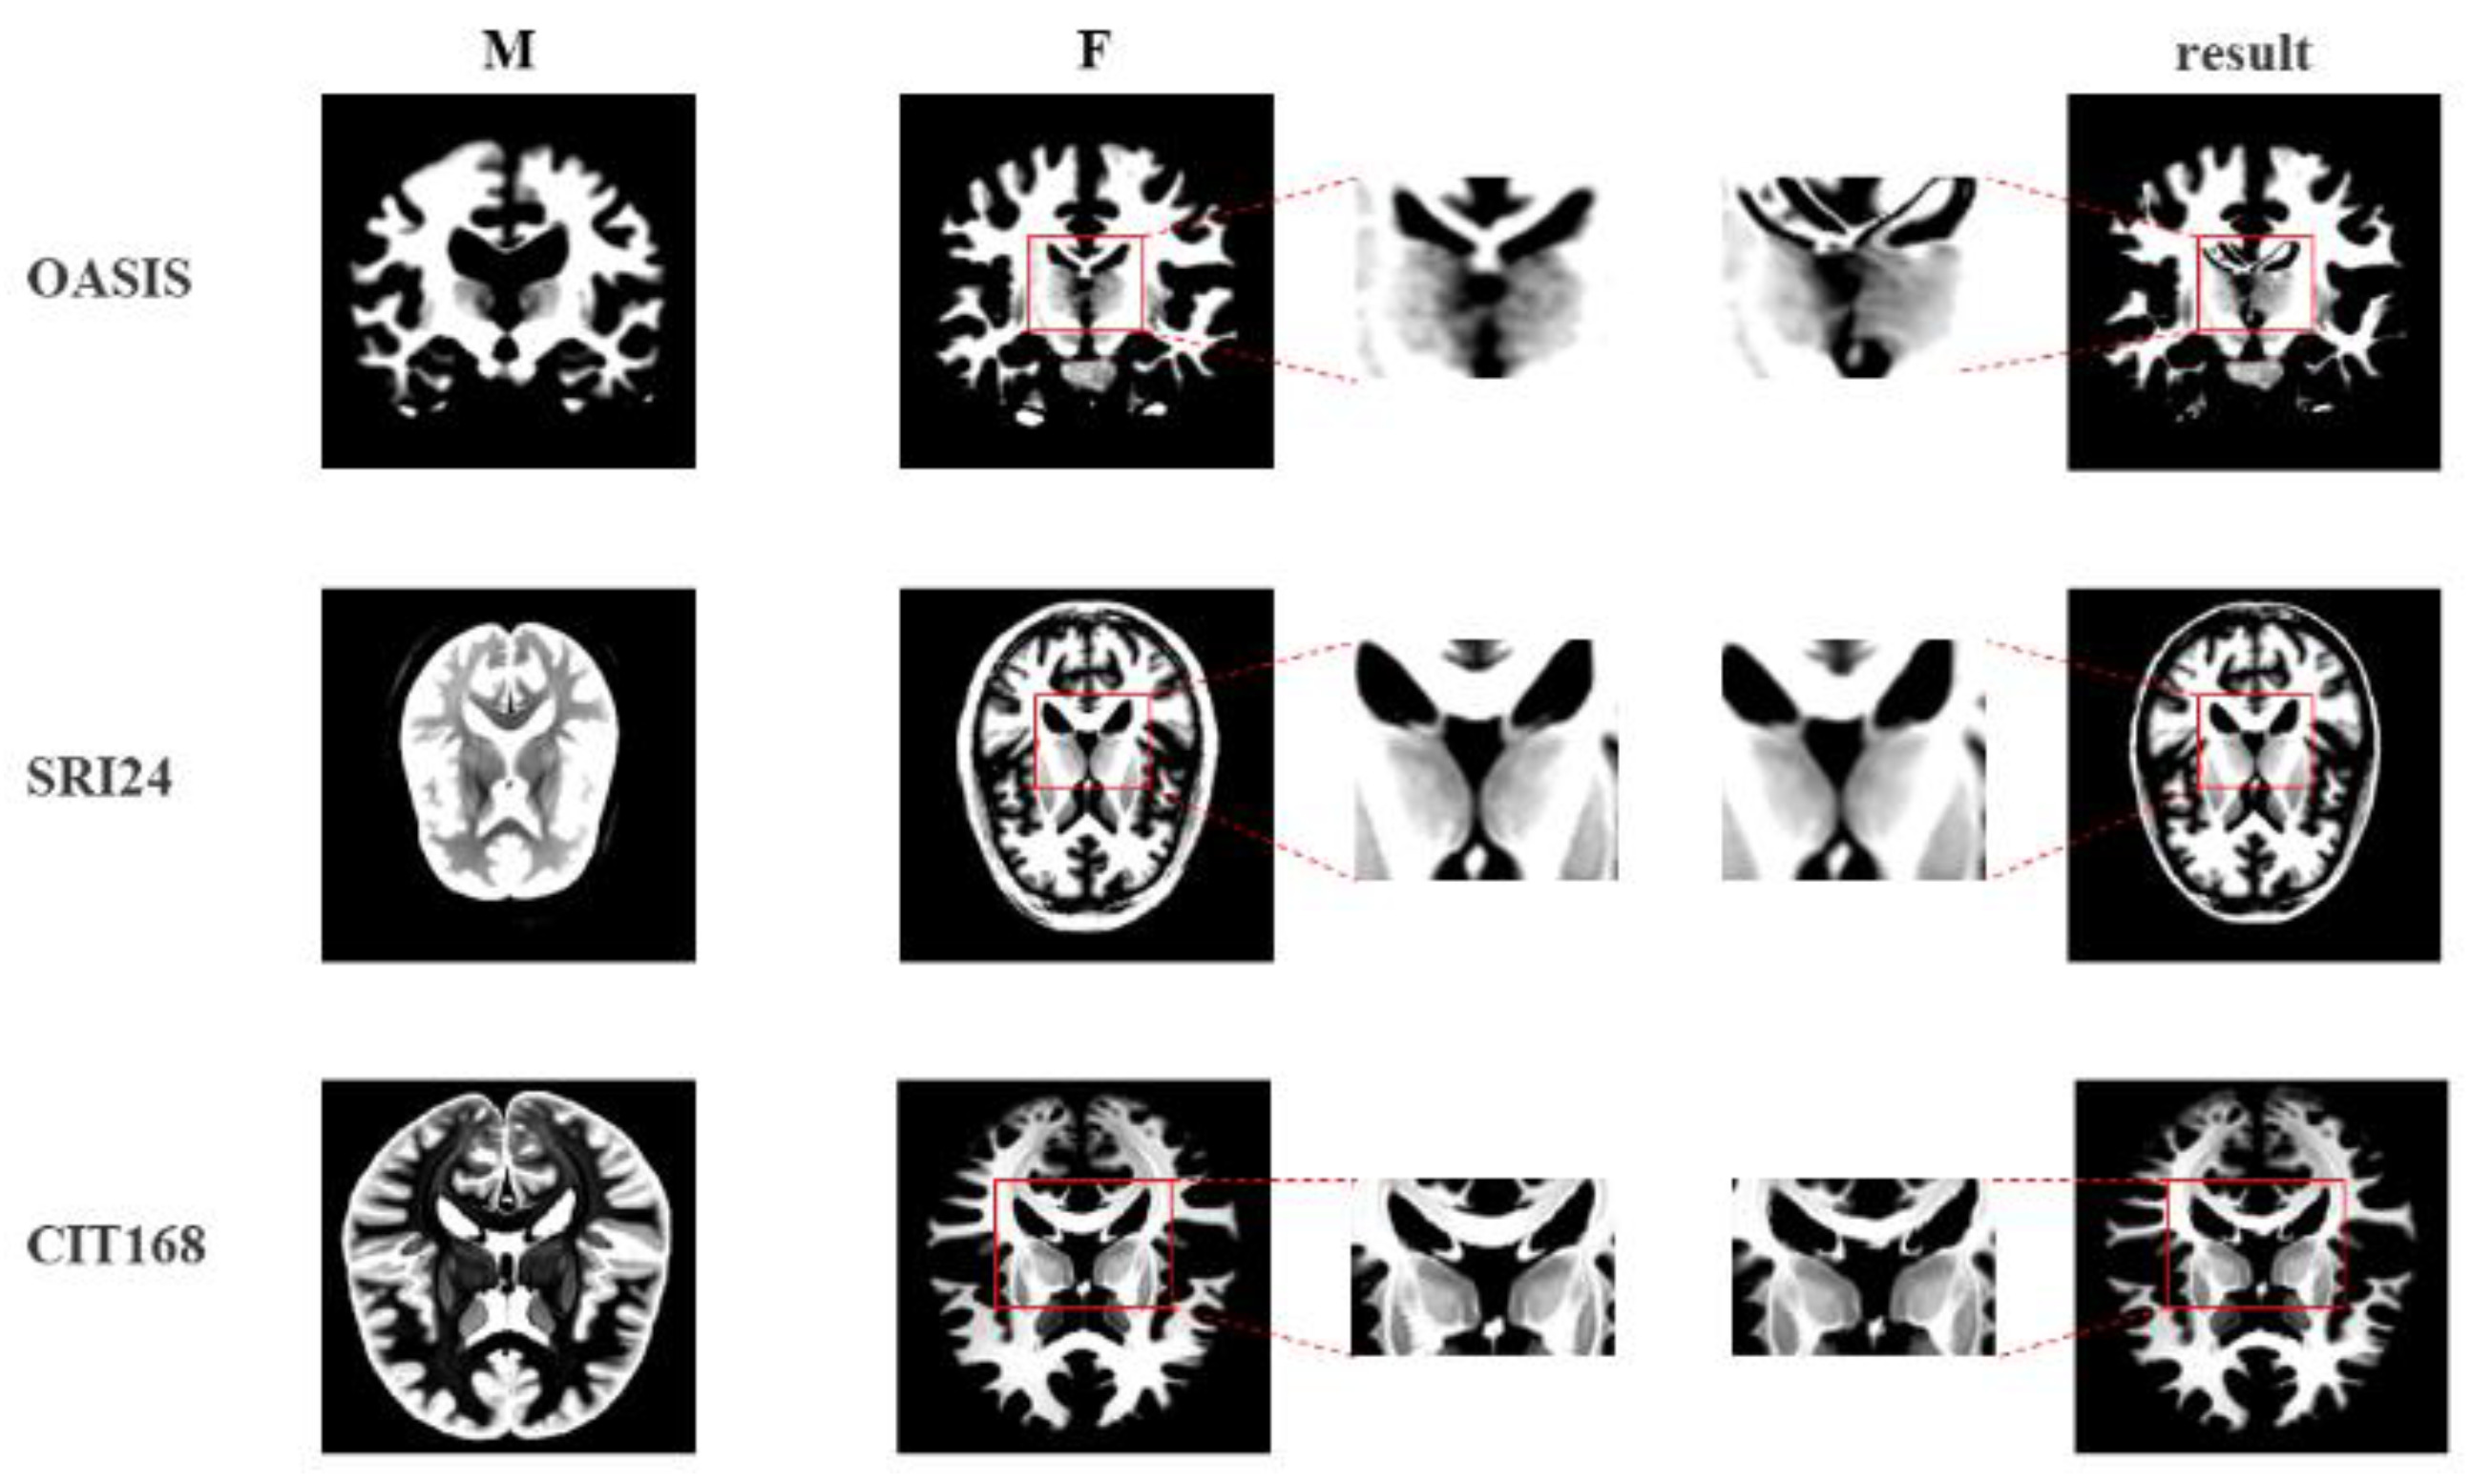

5.4. Evaluation and Analysis on CIT168, SRI24, and OASIS

| Method | SyN [1] | VoxelMorph [22] | VM-Diff [45] | Reverse-Net | |

|---|---|---|---|---|---|

| Dataset | |||||

| OASIS [42] | 67.7 ± 2.9 | 74.9 ± 13.7 | 75.2 ± 13.9 | 79.1 ± 1.3 | |

| SRI24 [44] | 70.3 ± 5.6 | 77.9 ± 2.4 | 78.6 ± 2.9 | 82.6 ± 0.6 | |

| CIT168 [43] | 67.8 ± 2.6 | 73.4 ± 3.9 | 73.2 ± 3.1 | 80.5 ± 1.9 | |